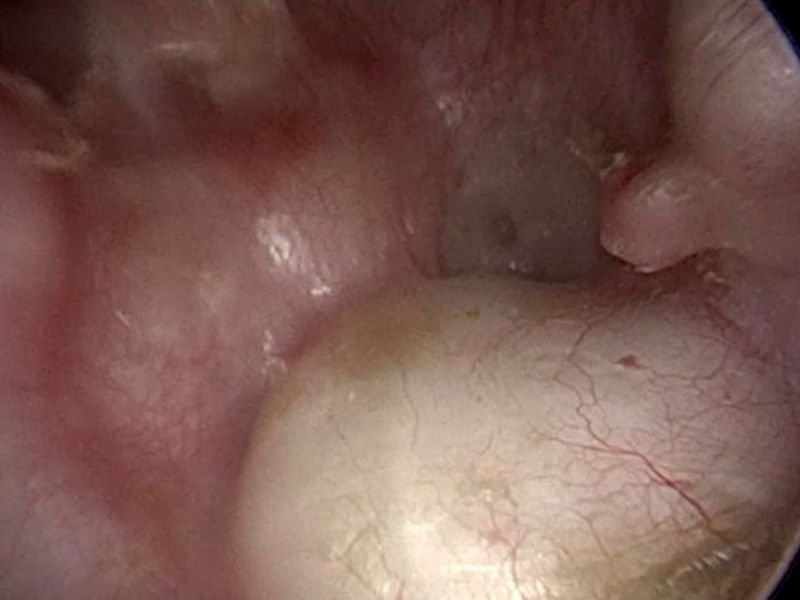

Além disso, o exame físico é essencial para observar sinais de inflamação ou secreção no ouvido médio. O uso do otoscópio, um dispositivo que permite a visualização do ouvido interno, é uma das principais ferramentas utilizadas para detectar a presença de fluidos no ouvido médio ou sinais de infecção. Em alguns casos, exames adicionais, como a audiometria, podem ser realizados para avaliar o impacto da infecção na audição do paciente.